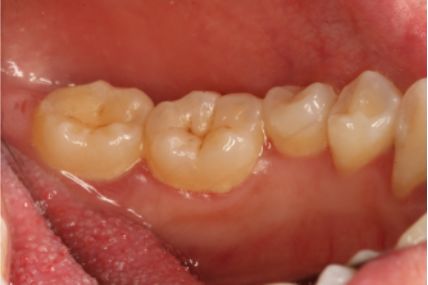

采用PT5牙周治疗仪进行全口超声龈上洁治术、超声龈下刮治术。术后5周复查可见牙龈炎症明显减轻,仍有轻度炎症,复查发现患者口腔卫生维护欠佳,再次进行口腔卫生宣教。

超声洁刮治术即刻